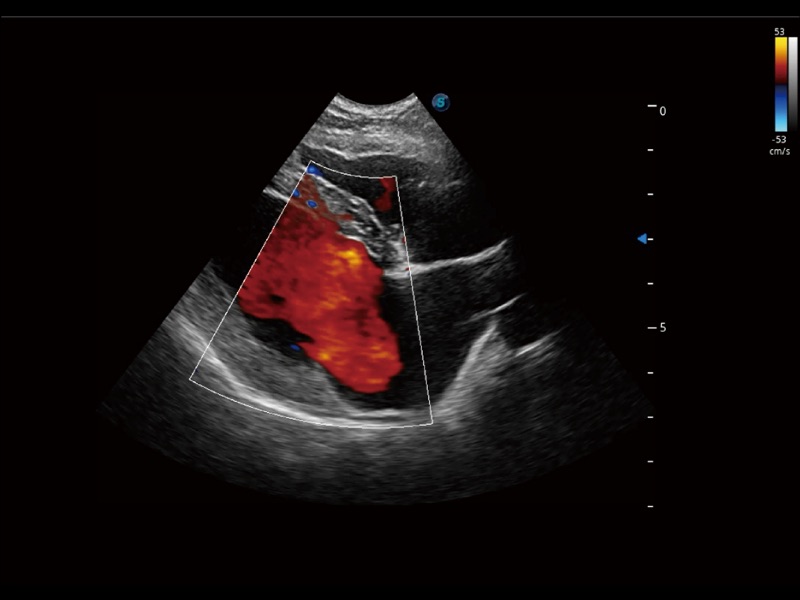

(犬)左室长轴血流

(犬)四腔心

(犬)胎儿主动脉弓立体血流

优异的基础图像

ProPet 70 全新的动物超声智能软件和丰富的探头群,为动物医生提供了高清晰度和精细分辨率的图像,无论在宠物、马科、畜牧还是实验室动物等应用中都可以轻松应对,为您的日常工作带来满意的体验。